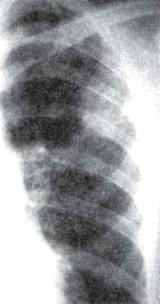

а б

Рис. 11.4. Бронхолобулярный инфильтрат во II сегменте правого легкого.

а - фрагмент рентгенограммы легких; б - фрагмент продольной томограммы в прямой проекции.

Бронхолобулярный инфильтрат обычно

характеризуется наличием в кортикальной зоне легочного поля, чаще в I,

II или IV

сегментах, ограниченного затемнения (фокусной тени) в основном малой

интенсивности, диаметром до 3 см. Инфильтрат имеет полигональную форму,

вытянутую по направлению к корню легкого, и размытые наружные контуры (рис.

11.4). КТ-исследование позволяет выявить просвет и деление мелкого бронха,

вокруг которого сформировался инфильтрат (рис. 11.5). Просвет бронха иногда

заполнен плотными казеозными массами. На томограмме бронхолобулярный инфильтрат

нередко выглядит как конгломерат из нескольких более или менее плотных мелких

очагов, объединенных зоной перифокального воспаления.